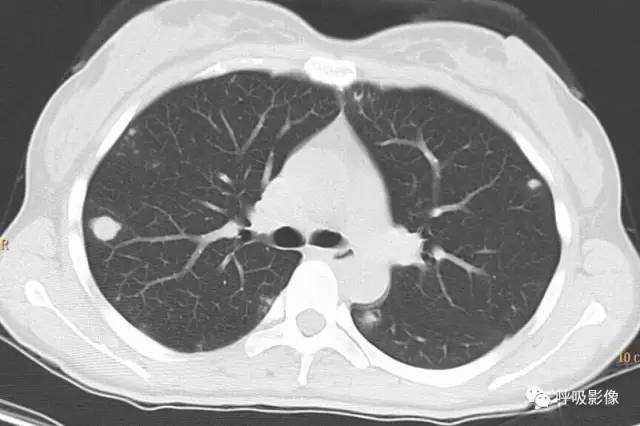

转移灶的影像早期可表现为不规则的小片状影或磨玻璃样阴影,逐渐增密、增粗,形成边缘不光滑的结节或肿块影,可伴出血,此时边缘毛糙,周围出现晕征、铺路石征等(图2)。

注意绒毛膜癌肺转移可以表现为单发。出血、晕征可以是早期表现。

图2 女,39岁 绒癌双肺转移伴肺内出血。可见肺内磨玻璃影和铺路石征。